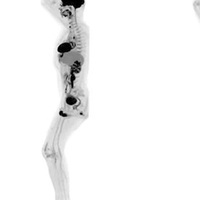

Michigan'daki Van Andel Ensititüsü'nde yapılan araştırma kapsamında 1.7 milyon kişinin son 50 yıldaki verileri incelendi.

Araştırmaya göre, Parkinson'un bağırsaklarda başladığına işaret eden bulgulara rastlandı ve apandisit ameliyatı geçirenlerin Parkinson'a yakalanma risklerinin yüzde 20 daha az olduğu görüldü.